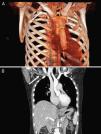

La paciente comenzó un mes previo con disnea a moderados esfuerzos. Cuando consultó en urgencias, presentaba disnea de reposo, debilidad, astenia y refería haber tenido un síncope. A la exploración presentaba PA de 120/80mmHg, FC de 110 lat/min y SatO2 del 95% sin O2 suplementario. Se apreciaba aumento del perímetro del miembro superior derecho, doloroso a la palpación y sin signos de empastamiento. La analítica presentaba perfiles bioquímico, hepático, renal, hemograma y coagulación dentro de la normalidad, excepto los dímeros D (2.500 ng/ml). La radiografía de tórax no presentaba ningún hallazgo significativo. Se realizó angioTAC de tórax, que mostró defectos de repleción intraluminal en las arterias segmentarias de ambas pirámides basales, lóbulos superiores, lóbulo medio y língula. Ante la presencia de tromboembolismo pulmonar bilateral y datos de inestabilidad clínica se decidió el ingreso en la unidad de cuidados intensivos (UCI) y la realización de fibrinólisis con rTPA. En el seguimiento posterior se realizó TAC de cuello, tórax, abdomen y pelvis (fig. 1 A y B), en la que se objetivó un espolón óseo a nivel de la clavícula derecha que comprimía la vena subclavia derecha e interrumpía parcialmente el retorno venoso. Los estudios de hipercoagulabilidad fueron negativos. La paciente fue intervenida mediante resección de espolón óseo clavicular, sección del músculo escaleno anterior y reconstrucción del periostio clavicular. Como complicaciones en el periodo posquirúrgico, presentó síndrome postrombótico del brazo derecho y hematoma en el músculo ilíaco izquierdo, con neuropatía femoral izquierda secundaria a la introducción del catéter venoso. Esto último le condicionó un periodo de meses de rehabilitación y el uso de silla de ruedas para su desplazamiento.

A) Reconstrucción tridimensional en la que se observa un espolón óseo a nivel de la clavícula derecha que comprime la vena subclavia e interrumpe parcialmente el retorno venoso (flecha). B) Corte coronal con reconstrucción multiplanar en el que se observa defecto de repleción de la vena subclavia derecha.